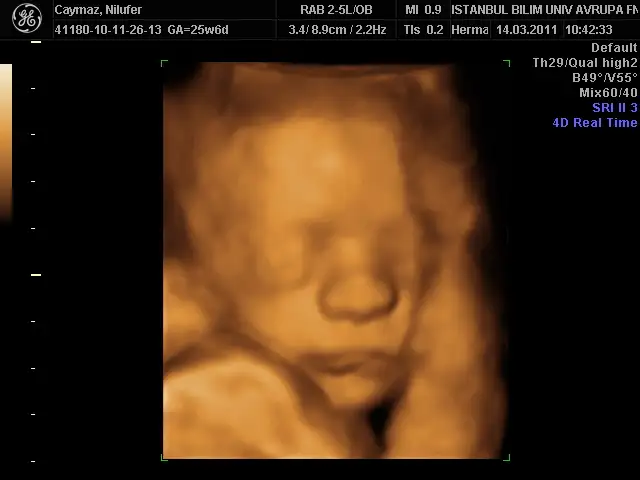

benimki 35 cm 1056 gr olmuş annesinin gülü dr önce rahmi çok ince budu 2,7 mm sonra sıkıştık tuvalalete öyle baktı çok şükür bir problem yokmuş bu sefer yüzünü bizden gizlemedi oğluşumm bence bana benziyor babasını kıl ediyorum bana benziyor diye kız olsa anlarım bana benzesin triplerini de diyor bu erkek banabenzicek diyo bi kıskanıyor bi kıskanıyor çok hoşuma gidiyorr

çok güzel pozlar vermiş oğluşun

oyyyyy çok masum yaaaa

çok tatlı maşallah

dudakları şişirmiş :)